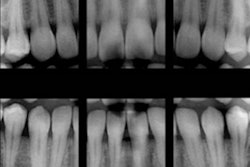

The usefulness of bitewing images for helping find caries in permanent teeth is well-established. But is the modality also useful in determining caries in primary teeth? Researchers compared the images to visual examination to find out.

The use of bitewing radiographs has been shown to help in the estimation of caries in permanent teeth, but there is a lack of clinical information on their use in primary teeth, particularly molars. The researchers wanted to see how bitewing radiography compared with clinical examination in detecting caries in primary molars.

Bitewing radiographs also were taken at the time of the clinical examination. A Belmont Belray 096-C (Belmont) system was used for the images.